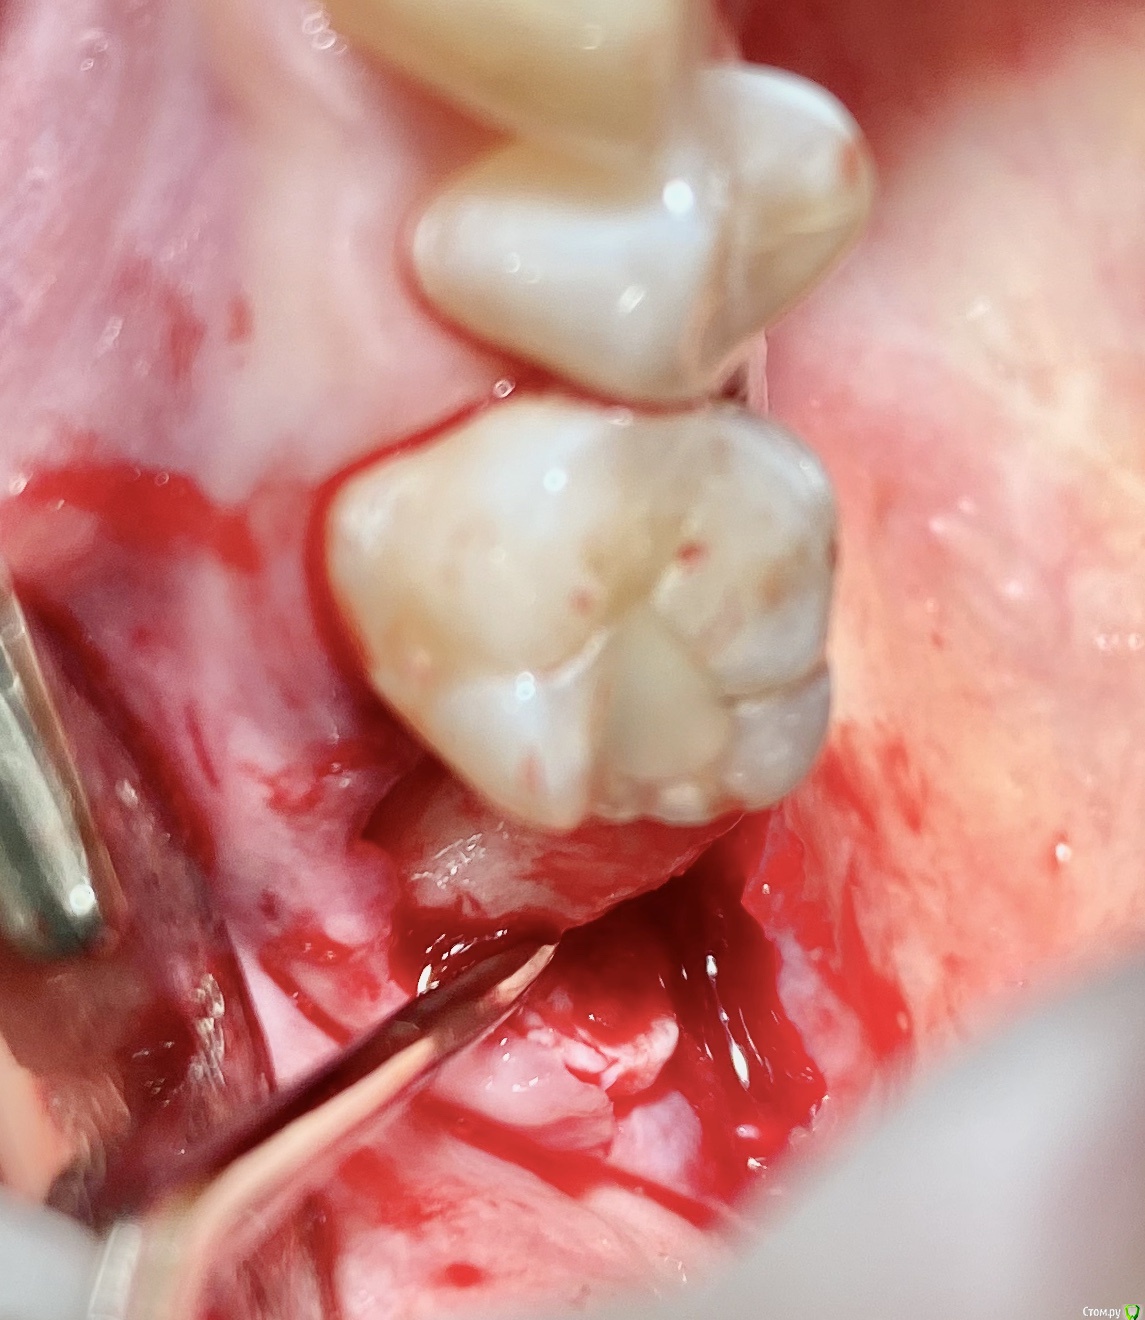

колесников Опубликовано 9 сентября, 2020 Поделиться Опубликовано 9 сентября, 2020 Т.е. на месте кривой это подслизистое отслоение, а где овал - это бугор, который нужно ротировать? овал-это бугор который мы видим и зачастую используем. Кривая-это бугор который можно забрать под слизистой. Конечно чем дальше к периферии ,тем его качество падает ,но он есть. Делаете поверхностный разрез ретромолярно,расщепляете,выделяете лоскут -заплатку,обрезаете её вестибулярно,дистально. Небно отступаете от края мм на 5 и проводите разрез до дистального края 7ки. Отделяете от основания. У вас получается заплатка на ножке. Перекидываете ее на гребень и вносите под вестибулярный край лоскута лунки,фиксируя матрасным швом. Далее придавливаете ножку перекидными швами небно-вестибулярно (ножек не прошиваем,только прижимаем). 3 Ссылка на комментарий

колесников Опубликовано 11 сентября, 2020 Поделиться Опубликовано 11 сентября, 2020 Перемещение бугра для закрытия лунки. Вестибулярно прикрепленную не смещаем. Вестибулярно компактной пластинки нет 9 Ссылка на комментарий